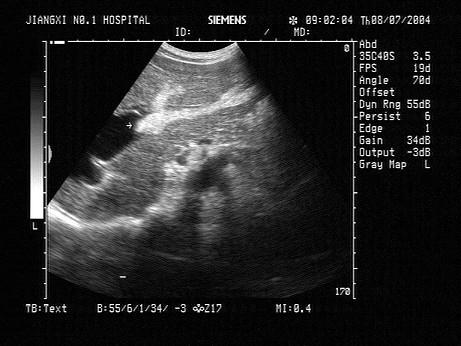

问题 女,38岁,上腹部经常疼痛,加重2天。声像图如图所示,诊断为?(?)

选项 A.左肝内胆管多发性结石 B.左肝血管瘤 C.左肝钙化灶 D.左肝内胆管蛔虫 E.左肝内胆管积气

答案 A